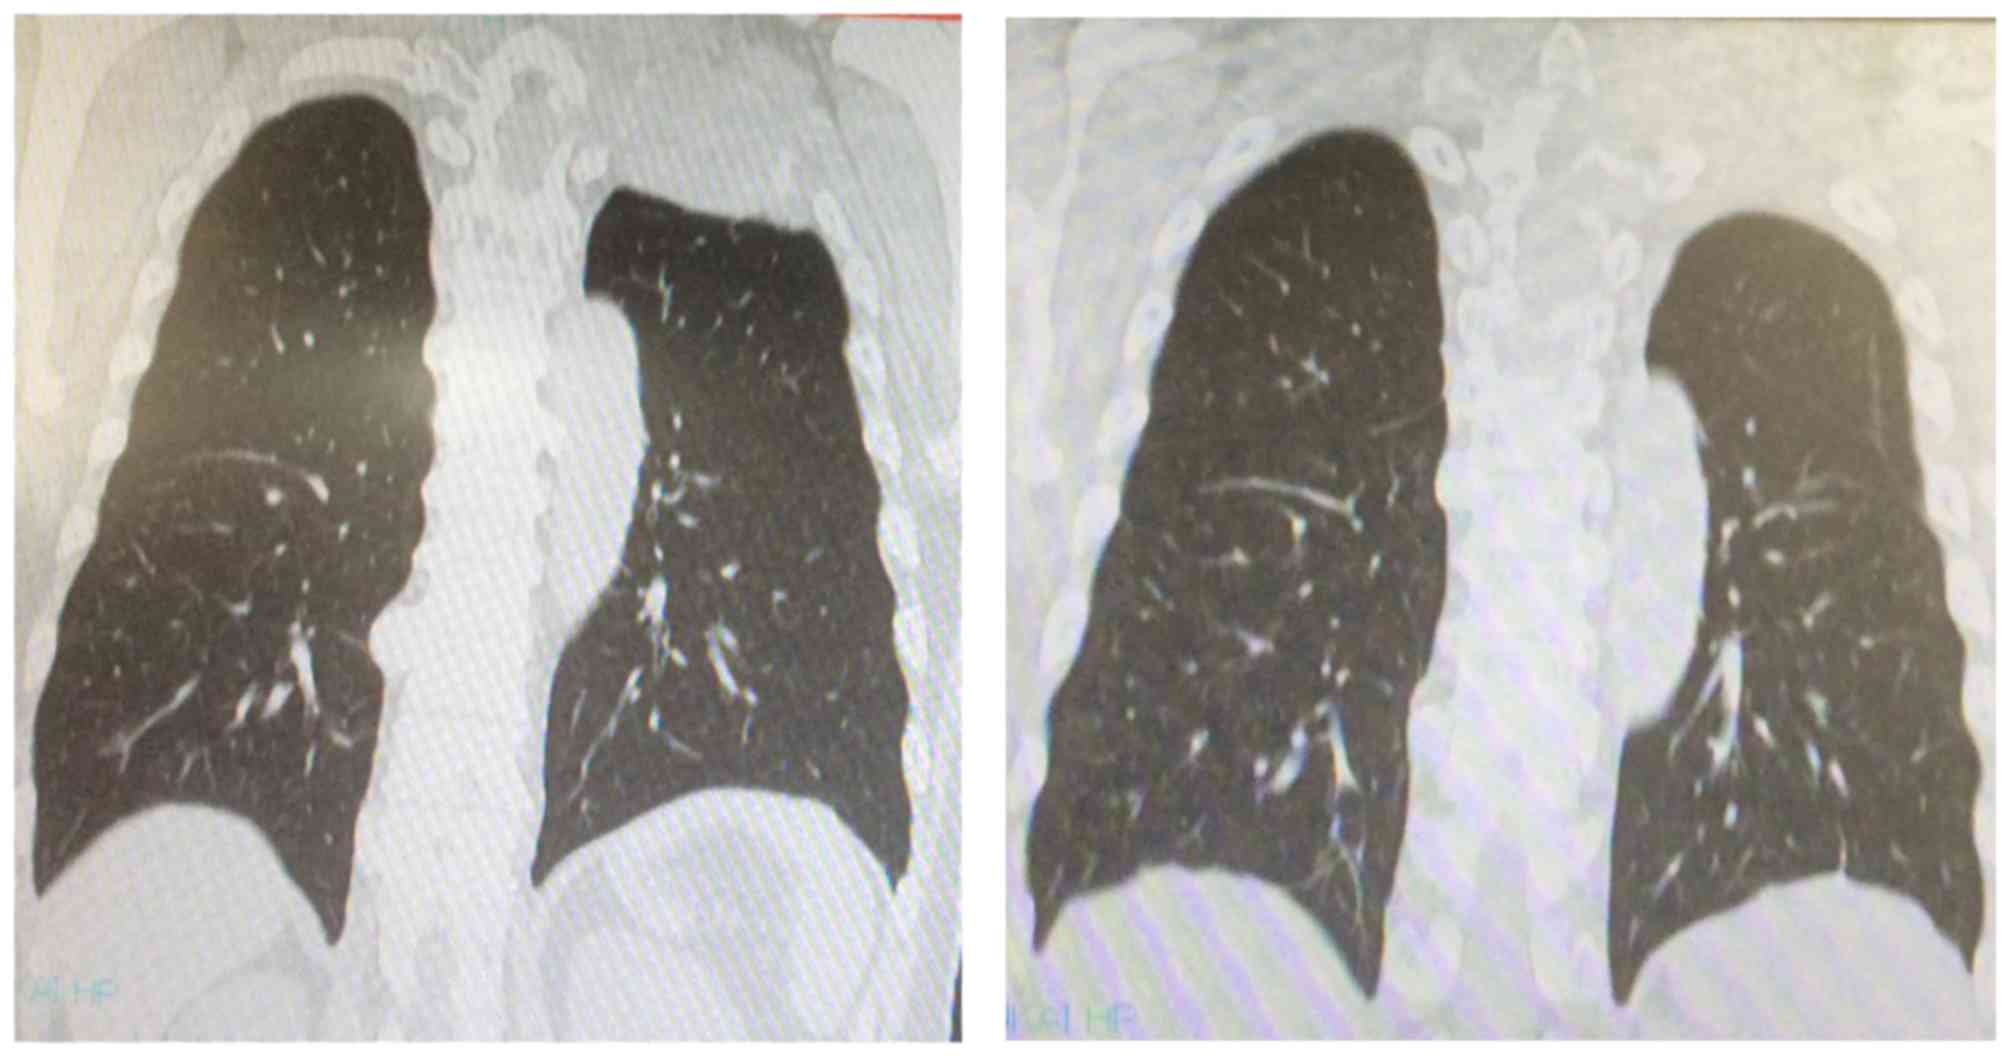

Case 6 was a 61-year-old male patient. At the

initial visit, an 8-cm mass was identified, extending from the

posterior aspect of the upper left lung to the chest wall,

infiltrating the ribs and the Th1 vertebral body, with partial

compression of the spinal cord. The computed tomography (CT) scan

revealed a 3-cm tumor in the inferior pole of the right kidney

(Fig. 1). CT-guided tumor biopsy of